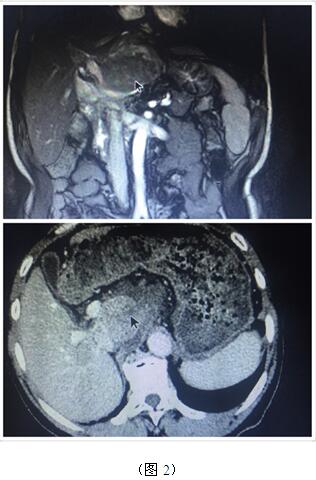

70歲高齡的曹奶奶是一個膽內膽管結石、膽總管結石、膽囊結石的高齡患者,由于結石部位多發(fā)(圖1),當地醫(yī)院多次住院治療,均建議開大刀切除部分肝臟;同樣患肝臟腫瘤的張爺爺,由于腫瘤位于肝臟尾葉,而且壓迫腹腔大血管(圖2),尋遍多家醫(yī)院都只能開腹手術切除,聽說衡陽市中心醫(yī)院腹腔鏡手術技術成熟遂慕名而來。肝膽外科周玖橋主任和李鑫副主任醫(yī)師仔細分析病情后決定為倆位患者行3D腹腔鏡手術。